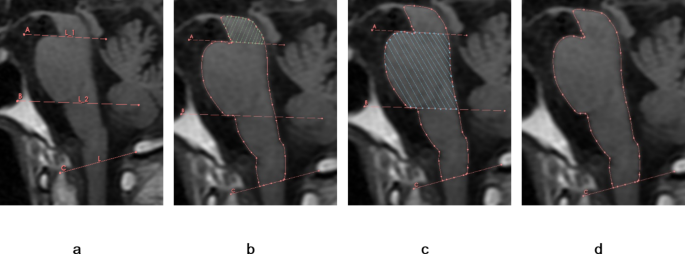

The brainstem is an irregular cylindrically shaped structure located beneath the cerebrum and connected rostrally to the diencephalon and caudally to the spinal cord at the foramen magnum. It consists of three major divisions, the midbrain, pons, and medulla oblongata. For quantitative measurements, a line (Line A) was drawn through the superior aperture of the pons to the inferior edge of the quadrigeminal plate and a second line (Line B) was drawn parallel to the first line but passing through the inferior aperture of the pons. A third line was drawn along the foramen magnum and defined as Line C (Line C) (Fig. 2a). The midbrain area was calculated as the area above Line A excluding the quadrigeminal plate (Fig. 2b), the pontine area as the area between the anterior and posterior edges of the pons and between Lines A and B (Fig. 2c), and the brainstem area as the sum of the midbrain, pons, and medulla oblongata areas (up to the foramen magnum line) (Fig. 2d). The midbrain, midbrain plus pons, and midbrain plus pons plus medulla oblongata areas were measured in the sagittal plan including the aqueduct to calculate the indicated ratios.

Analysis of brainstem areas in the sagittal plane containing the mesencephalic aqueduct. (a) Upper and low boundaries of the brainstem. Line A passes through the superior cerebellar peduncle (upper limit of the pons) and the lower edge of the quadrigeminal plate, while Line B is parallel to Line A and passes through the inferior cerebellar peduncle (lower limit of the pons). Line C is drawn along the foramen magnum (lower limit of the medulla). (b) Midbrain area above Line (A) (c) Pontine area between Lines A and (B) (d) Total brainstem area.